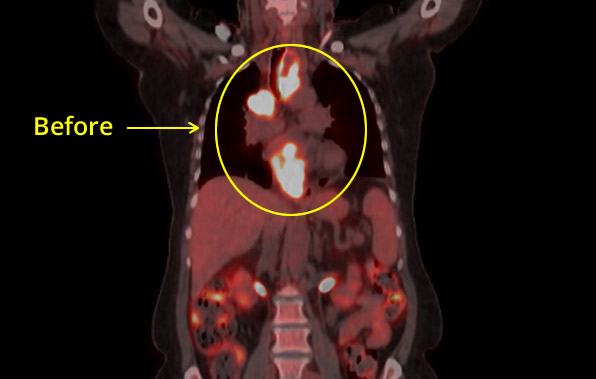

Esophageal CXR Before

Esophageal CXR After